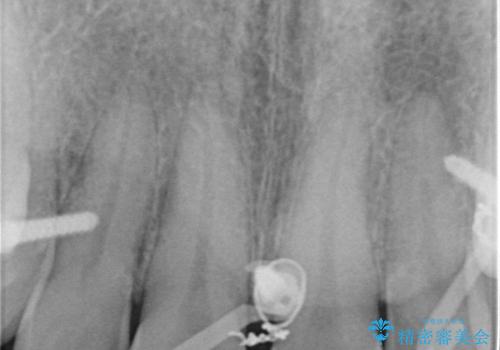

歯の神経は生きていますが、精度の高い被せもののため冷たいものがしみるなどの症状もなく、きれいになったと満足していました。

- 転んで欠けてしまった前歯を治したいと来院された患者様です。